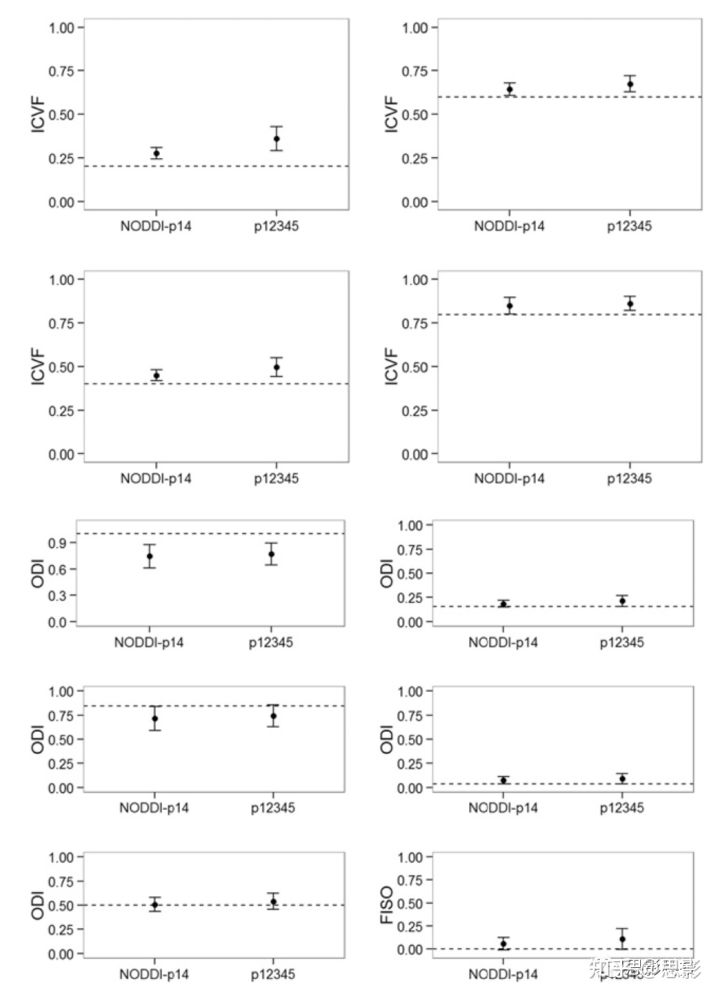

本研究使用整个HYDI数据集进行NODDI计算。虽然HYDI采样方案比推荐的NODDI采样方案具有更多的扩散方向,但大约有2/3的扩散信号处于较高的b值和较低的信噪比(SNR)。通过计算机仿真验证了使用HYDI方案进行NODDI计算的兼容性。图8为SNRb0 = 20下的仿真结果,与本研究中估算的人类HYDI数据的白质信噪比相似。在b =0 s/mm2时,47名受试者整个脑白质的SNR约为21±7。其他SNR的仿真结果如图S2所示。在SNRs和ICVF-ODI组合的范围内,推荐的NODDI方案与HYDI方案之间无显著性差异(p>0.05)。在SNRb0 = 20时,HYDI比NODDI-p14更容易高估低的ICVF,但两者在高ICVF(>0.5)时是可比较的,对于白质来说关于高ICVF的比较更切实际(表S3)。两种方案都低估了高ODI,但在低ODI(<=0.5)下表现得很好,这对白质来说更切实际(表S3)。